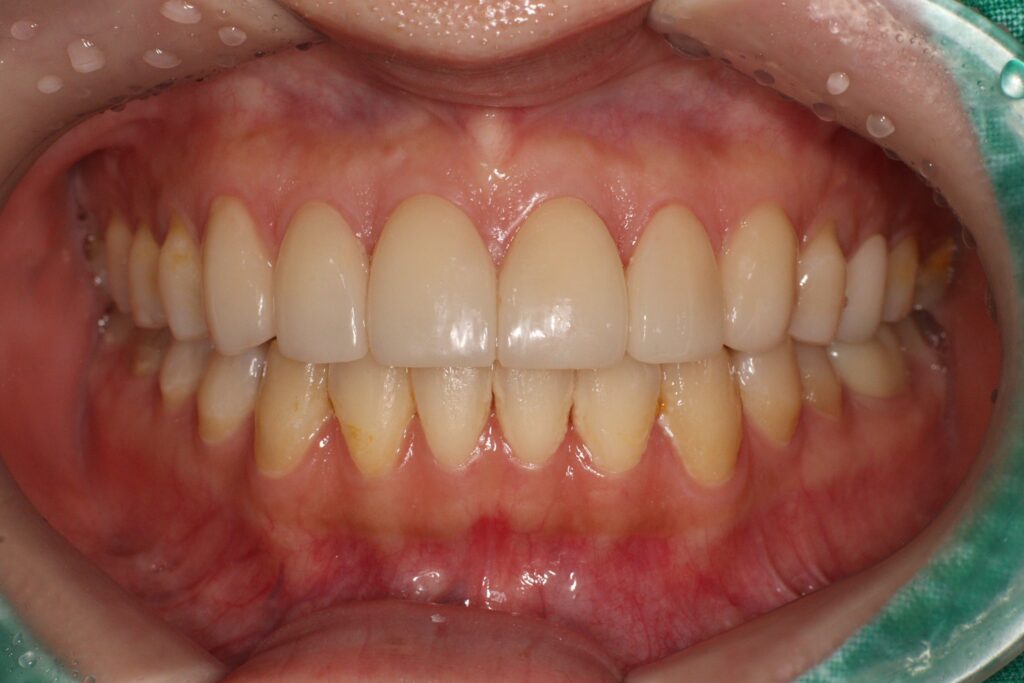

전체적으로 인레이 6개, 근관치료 1개,

크라운 2개, 레진 6개 등 총 20개 치아에 대한

치료가 이루어졌으며,

이를 통해 심미적인 개선과 더불어

기능적인 안정성까지 함께

확보할 수 있었습니다.

치료 후에는 치아의 색상과 배열,

형태가 자연스럽게 어우러지며

환자의 만족도를 높일 수 있었습니다.